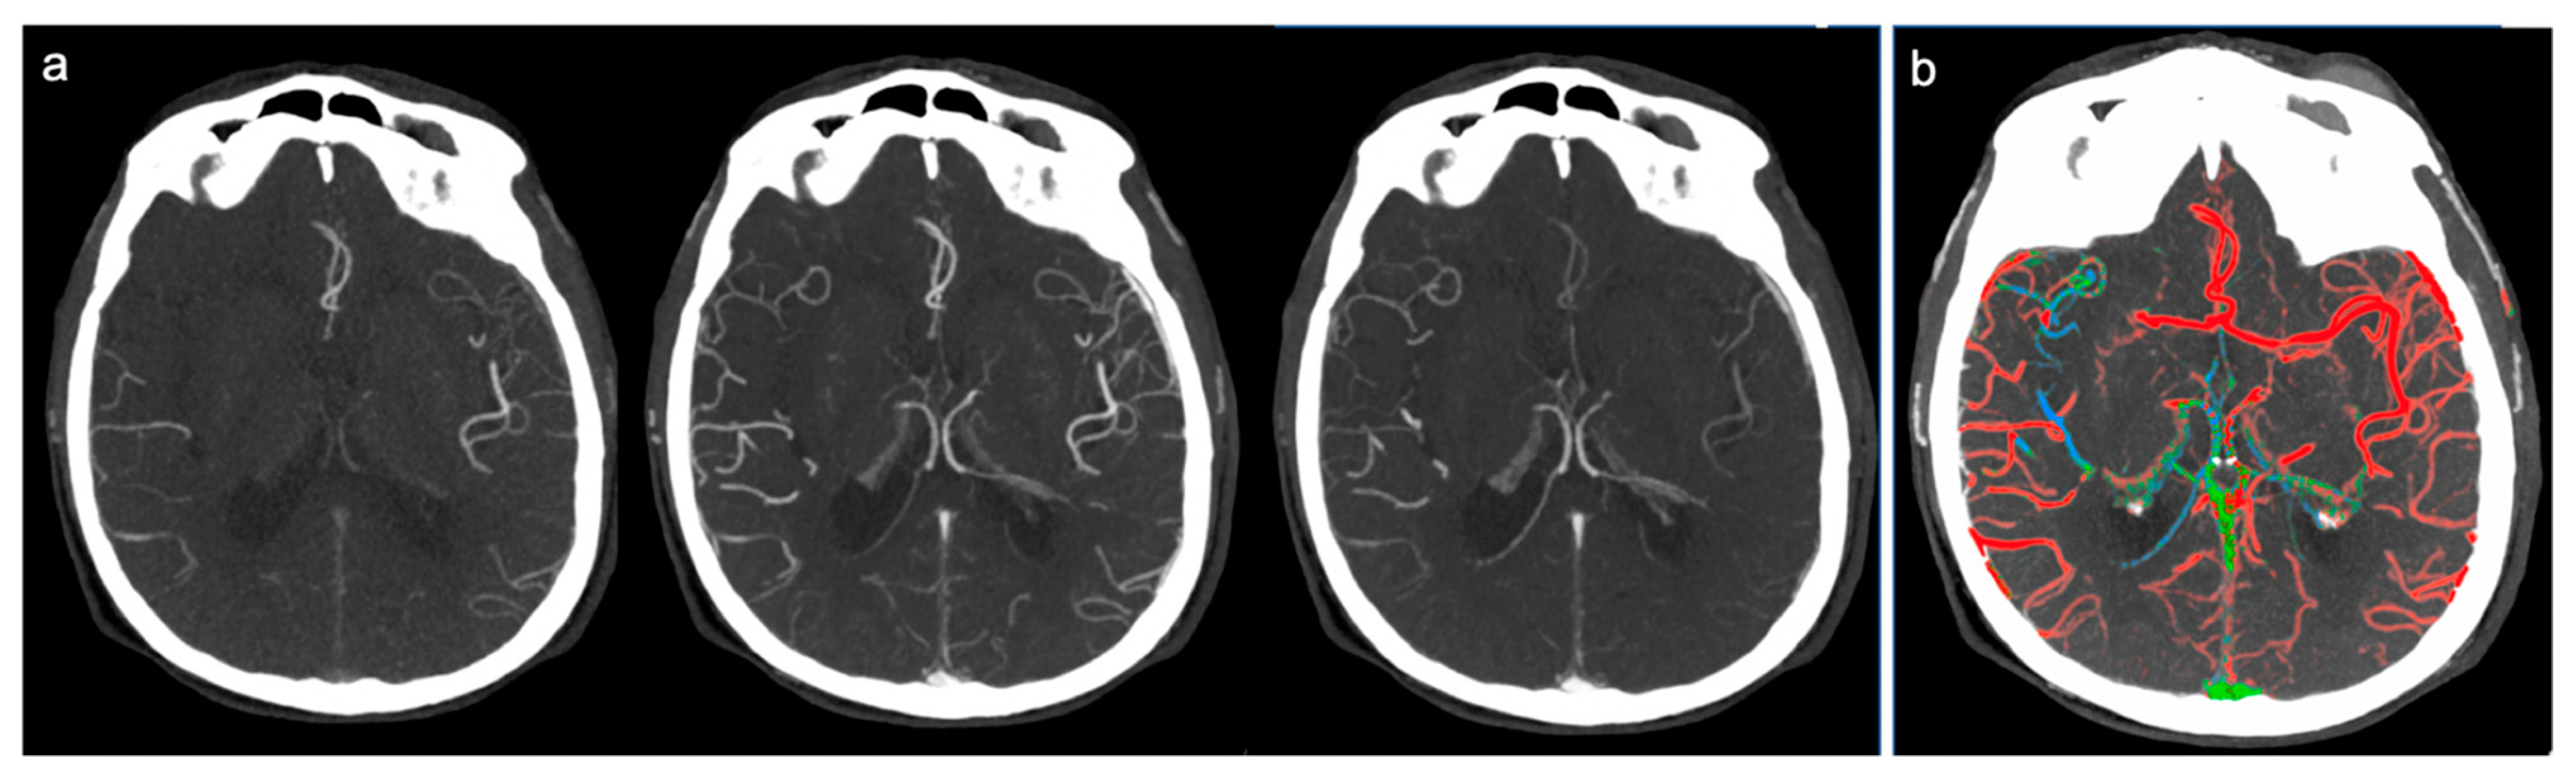

Figure 1.

Example of good collateral circulation at ColorViz. (a) mCTA shows a right-sided M1 segment occlusion with good pial artery filling (1 phase delay); (b) ColorViz map shows predominant red vessels in the affected territory downstream from the occlusion (score of 3).